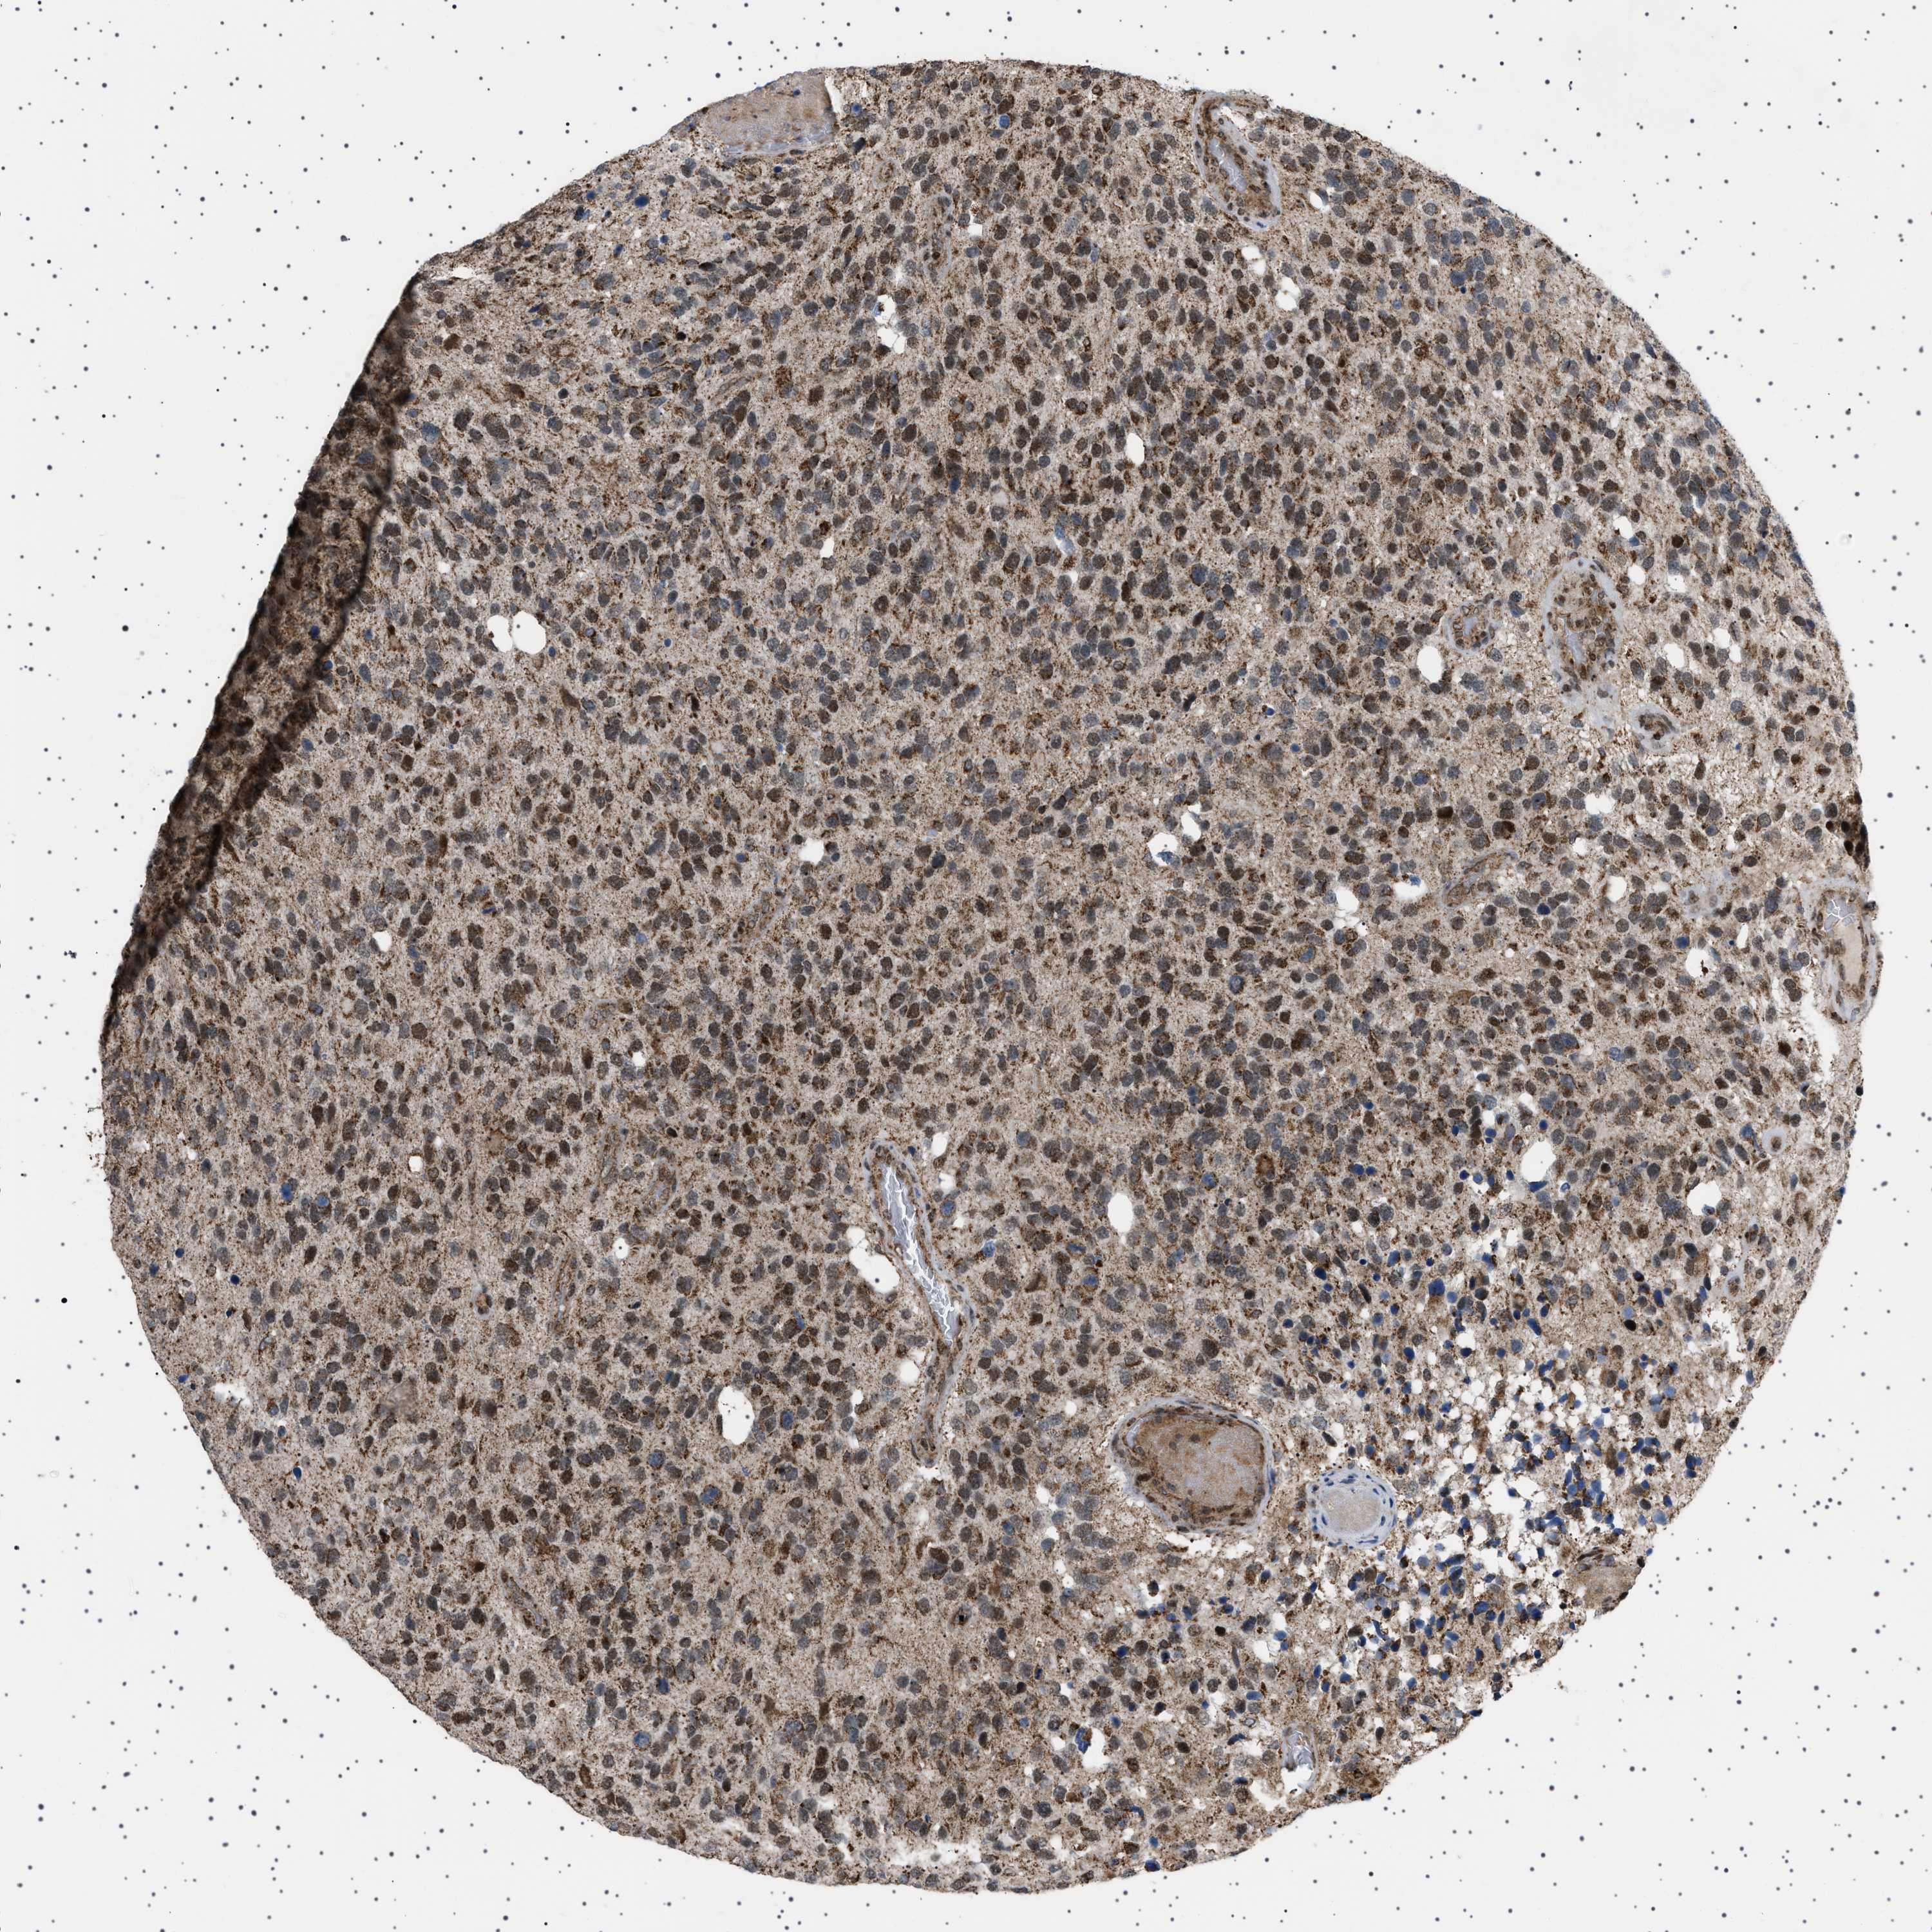

GLIOMA - Protein expressioni

A mouse-over function shows sample information and annotation data. Click on an image to view it in a full screen mode. Samples can be filtered based on level of antibody staining by selecting one or several of the following categories: high, medium, low and not detected. The assay and annotation is described here.

Note that samples used for immunohistochemistry by the Human Protein Atlas do not correspond to samples in the TCGA dataset.

Antibody stainingi

Antibody staining in the annotated cell types in the current human tissue is reported as not detected, low, medium, or high, based on conventional immunohistochemistry profiling in selected tissues. This score is based on the combination of the staining intensity and fraction of stained cells.

Each image is clickable and will lead to virtual microscopy that enables deeper exploration of all samples and also displays staining intensity scores, fraction scores and subcellular localization as well as patient and tissue information for each sample.

Antibody HPA017214

Staining

High

Medium

Low

Not detected

Intensity

Strong

Moderate

Weak

Negative

Quantity

>75%

75%-25%

<25%

None

Location

Nuclear

Cytoplasmic/membranous

Cytoplasmic/membranous,nuclear

Glioma, malignant, High grade

Glioma, malignant, Low grade